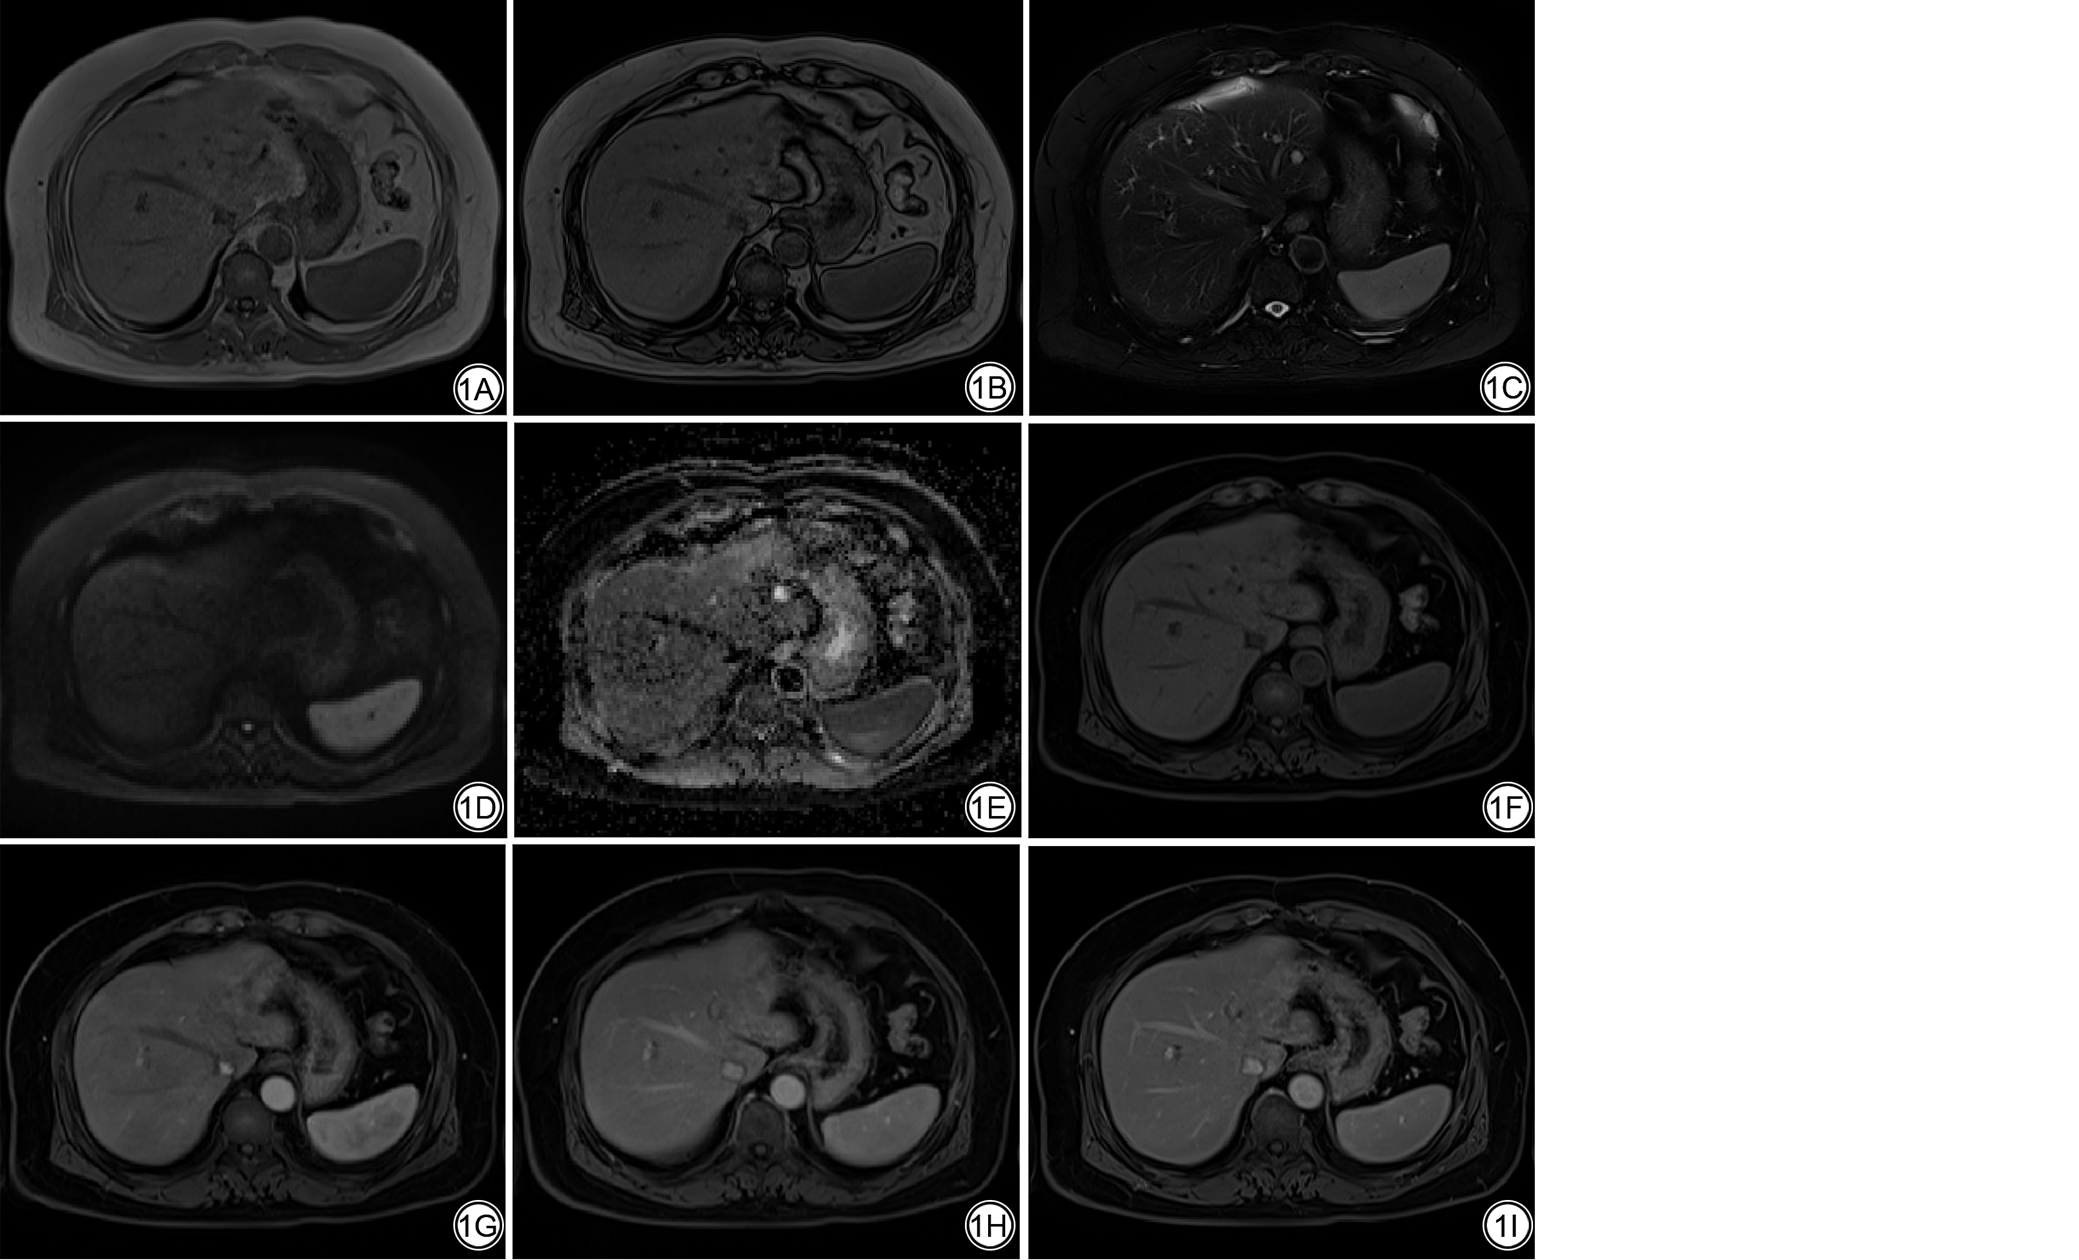

根据我院AI研究流程,首先定义研发肝脏mpMRI序列分类AI模型用例,包括:模型ID、临床任务、临床应用场景、调用流程、输入输出数据等。模型的输出结果定义为9个类别:T1WI同相位(T1WI in-phase, T1WI_In)、T1WI反相位(T1WI opposed-phase, T2WI_Opp)、T2WI脂肪抑制序列(T2WI with fat suppression, T2WI_Fs)、高b值DWI(high b value DWI, DWI_High)、ADC以及DCE的增强前(pre enhanced, DCE_Pre)、动脉期(arterial phase, DCE_AP)、门脉期(portal venous phase, DCE_PVP)、延迟期(delayed phase, DCE_DP)图像。肝脏mpMRI序列名称和定义见表1图1

图1  肝脏mpMRI图像序列类别示例。肝囊肿患者,男,60岁,肝左叶占位。1A:T1WI同相位;1B:T1WI反相位;1C:T2WI脂肪抑制序列;1D:高b值扩散加权成像;1E:表观扩散系数图;1F:DCE 增强前;1G:DCE动脉期;1H:DCE门脉期;1I:DCE延迟期。mpMRI:多参数磁共振成像;DCE:动态对比增强扫描。

Fig. 1  Examples of liver mpMRI image sequence categories. Hepatic cyst, male, 60 years old, lesions in the left lobe of liver. 1A: T1WI in-phase; 1B: T1WI opposed-phase; 1C: T2WI with fat suppression; 1D: High b-value diffusion-weighted imaging; 1E: Apparent diffusion coefficient map; 1F: DCE-pre enhanced; 1G: DCE- arterial phase; 1H: DCE-portal venous phase; 1I: DCE-delayed phase. mpMRI: multi-parameter magnetic resonance imaging; DCE: dynamic contrast-enhanced.